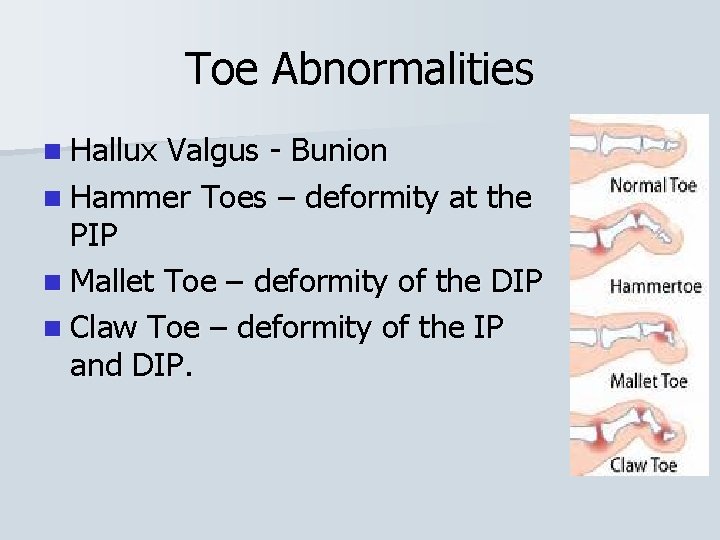

Toe Abnormalities n Hallux Valgus - Bunion n Hammer Toes – deformity at the PIP n Mallet Toe – deformity of the DIP n Claw Toe – deformity of the IP and DIP.